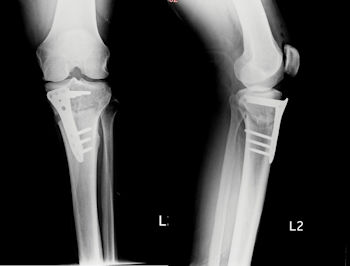

Menisküs onarımına ek olarak, eklem içinde gerekli kıkırdak girişimleri yapılmalı, bacakta varolan eğrilikler kemik ameliyatı ile düzeltilerek yük aksının yırtık bölgesinden geçmesi engellenmelidir. Doktorunuz, ameliyat öncesi aks grafileri ile bu işlemin gerekli olup olmadığına karar verecektir. (Resim 4)